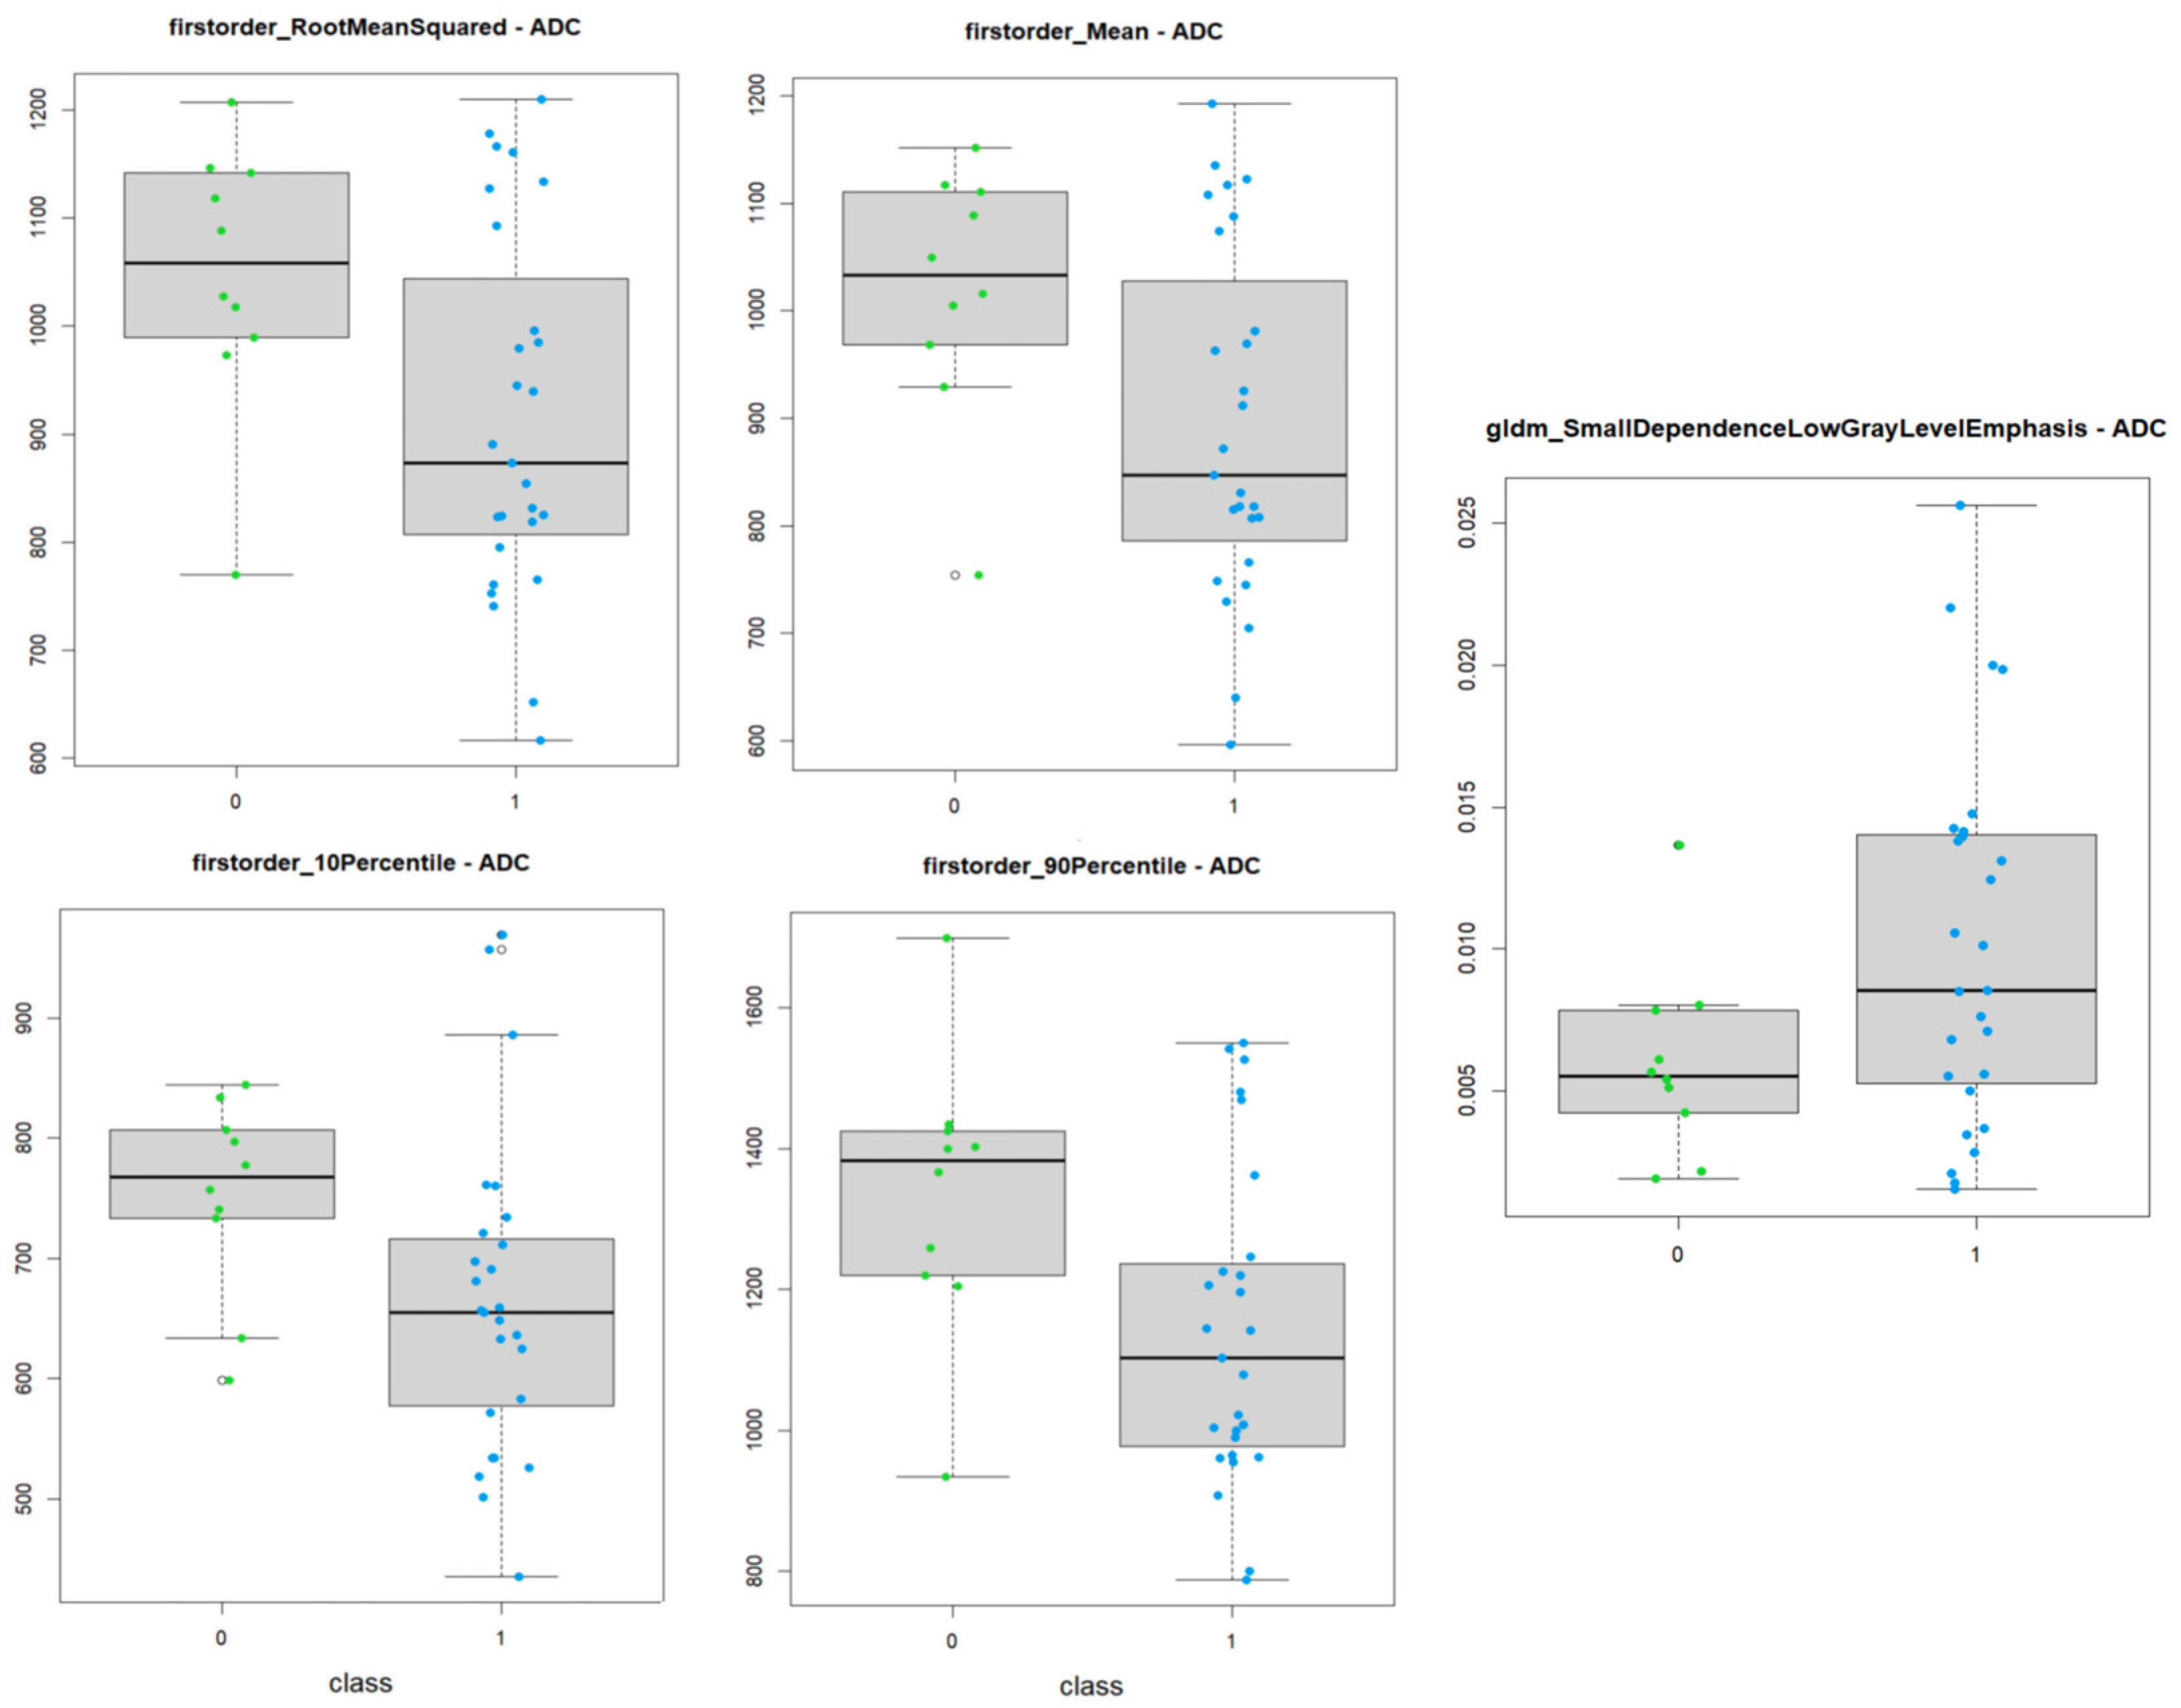

3.1. ADC Maps

- 9 First order features;

- 4 Gray Level Co-occurrence Matrix features;

- 1 Gray Level Dependence Matrix feature;

- 2 Gray Level Size Zone Matrix features.

| firstorder_10Percentile | t-test | 0.020 |

| firstorder_90Percentile | t-test | 0.022 |

| firstorder_Mean | t-test | 0.017 |

| firstorder_RootMeanSquared | t-test | 0.017 |

| gldm_SmallDependenceLowGrayLevelEmphasis | t-test | 0.017 |